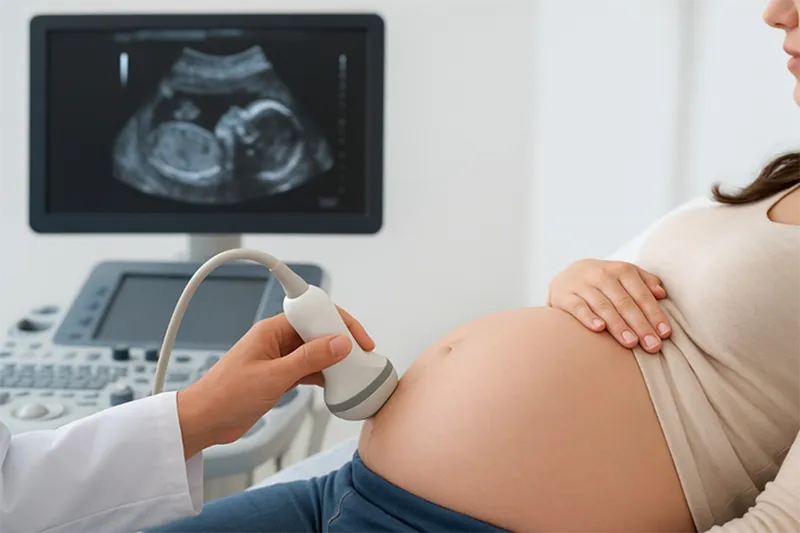

چرا نباید در دوران بارداری بیش از حد از سونوگرافی استفاده کنیم؟ سونوگرافی بارداری، یکی از مؤثرترین روش های بررسی وضعیت جنین است که در تمام مراحل بارداری از اهمیت فراوانی برخوردار است. این روش به مادر و پزشک کمک می کند تا رشد، موقعیت و سلامت جنین را ارزیابی کرده و در صورت وجود مشکل، اقدامات درمانی لازم را به موقع انجام دهند. با این حال، استفاده بی رویه از سونوگرافی بارداری می تواند نگرانی های غیر ضروری و هزینه های اضافی به همراه داشته باشد.

سونوگرافی بارداری، به مادران کمک می کند تا از سلامت و رشد طبیعی جنین خود اطمینان حاصل کنند. در مراحل ابتدایی بارداری، این روش برای تأیید بارداری و تشخیص محل قرارگیری جنین (داخل رحم یا خارج از آن) استفاده می شود. در مراحل بعدی نیز، سونوگرافی برای ارزیابی وضعیت جفت، مایع آمنیوتیک، ضربان قلب جنین و تشخیص ناهنجاری های احتمالی مانند سندرم داون یا نقایص مادرزادی کاربرد دارد. بنابراین، انجام سونوگرافی بارداری از اهمیت بالایی برخوردار است و نقش حیاتی در تشخیص زود هنگام مشکلات احتمالی دارد.

سونوگرافی بارداری از امواج فراصوت با فرکانس بالا استفاده می کند که به طور طبیعی در بدن وجود ندارند. این روش به عنوان یکی از اصلی ترین ابزارهای پایش سلامت جنین شناخته می شود و در حالت عادی، بی خطر و غیر تهاجمی است. با این حال، انجام بیش از حد سونوگرافی ضرورتی ندارد؛ به ویژه زمانی که دلایل پزشکی کافی برای انجام آن وجود ندارد. برخی مادران برای داشتن تصاویر یادگاری از جنین خود، دفعات زیادی سونوگرافی انجام می دهند که از نظر علمی توصیه نمی شود. به همین دلیل، پزشکان تأکید دارند که سونوگرافی بارداری باید تنها در مواقع ضروری و بر اساس تشخیص پزشک و بازه های زمانی مشخص انجام شود.